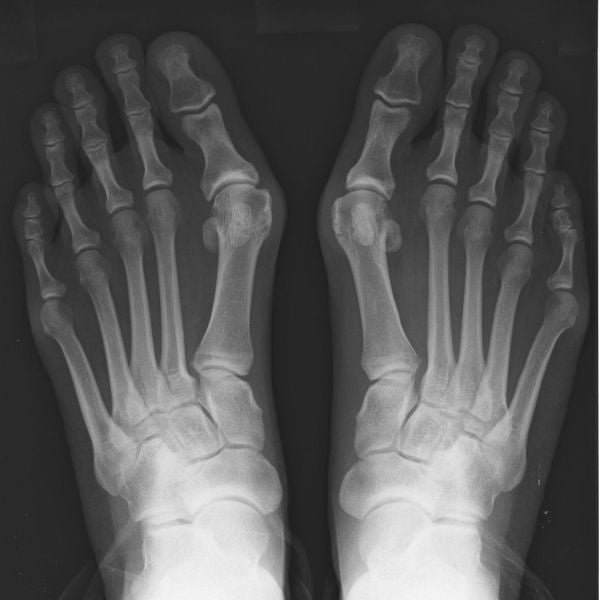

Ursachen von Hallux Valgus

Zu enge Schuhe, schwache Fußmuskeln und Fehlbelastung sind die häufigsten Ursachen.